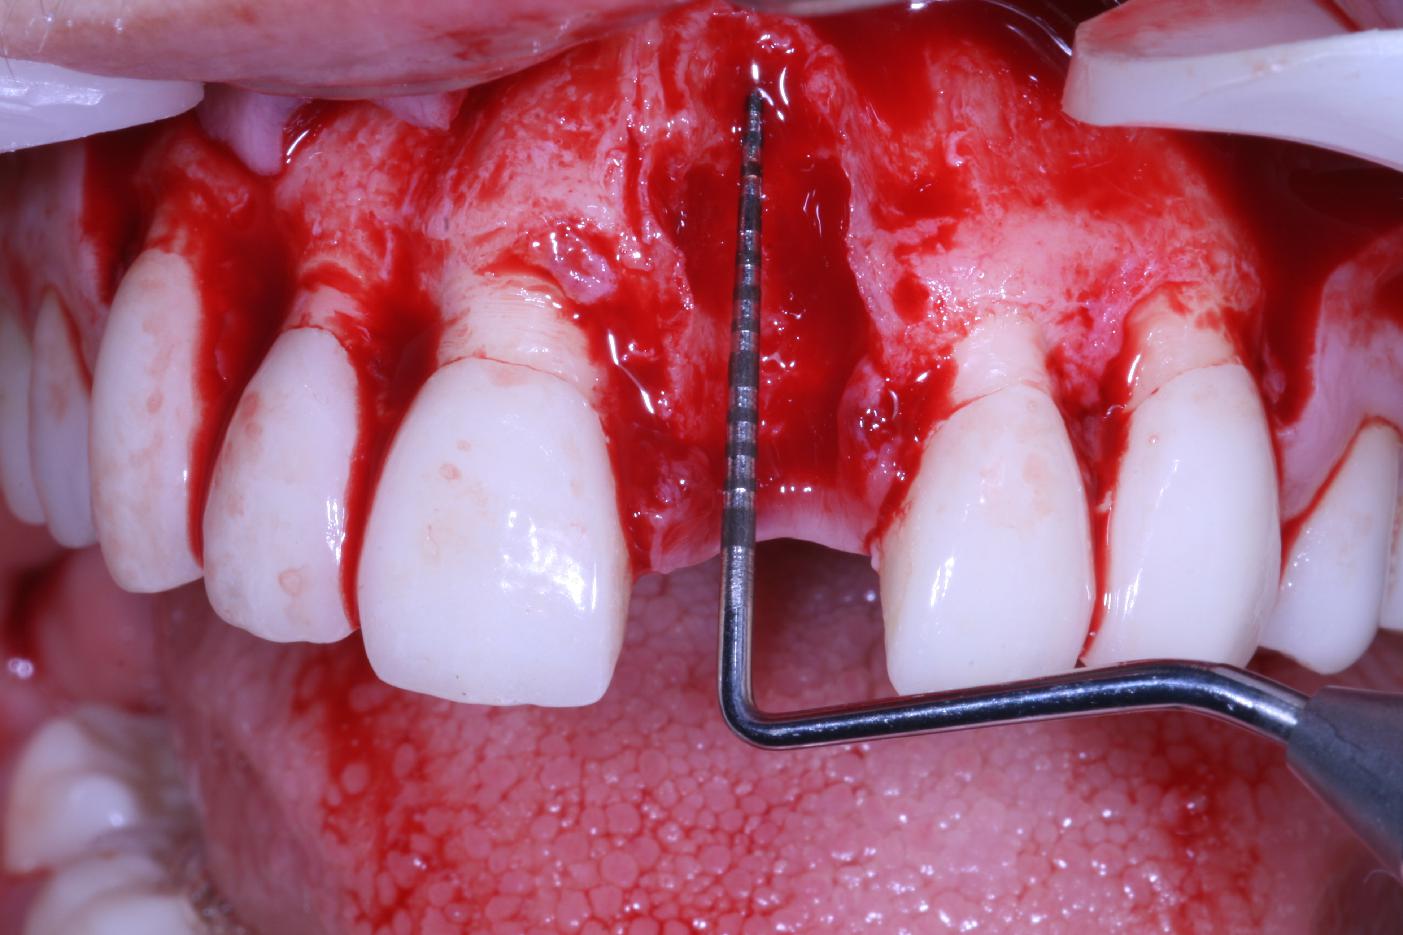

Mucosal thickening around bone level implants - Dr. A. Puisys

Full-thickness flap preparation bucally and lingually